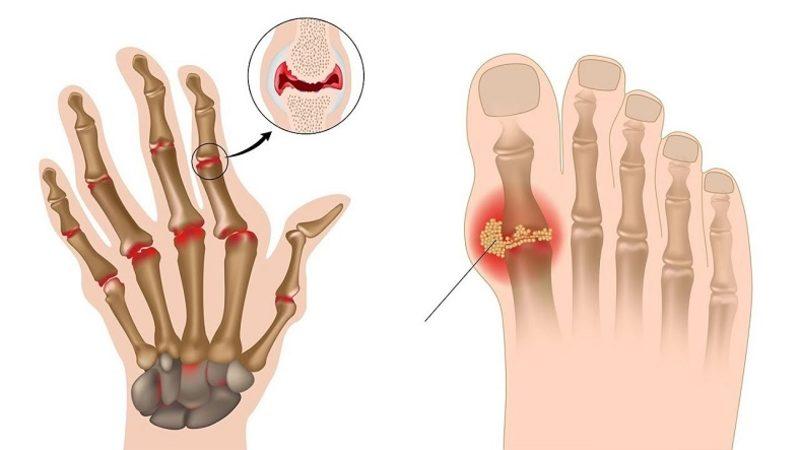

Gut hastalığı en geniş tanımıyla bir eklem iltihabı hastalığıdır. Genel olarak fazla protein alımı sonrası kana karışan ürik asit birikir ve dışarı atılamaz. Dışarı atılmayan ürik asit ayak başparmağı başta olmak üzere diğer ayak eklemlerinde kristalleşerek ağrı ve hassasiyete neden olan bir iltihap oluşturur.

Gut atağının çoğu zaman ilk ortaya çıktığı yer ayak başparmağı eklemidir. Ayak bileği, diz ve ilerleyen zamanlarda omurga sisteminde bile iltihap oluşturabilir. Gut atağı her zaman eklemlerde meydana gelir çünkü ürik asit gece kan sıcaklığı azalınca eklemlerde toplanarak kristalize bir hal alır.